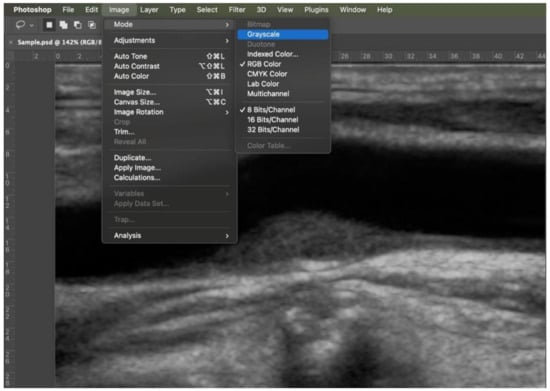

First step: color information was eliminated by transforming a red, green, blue (RGB), 8 bit image into a grey scale, 8 bit image (Figure 2).

Figure 2.

Step 1: transformation into a grey scale 8 bit image (Image > Mode).